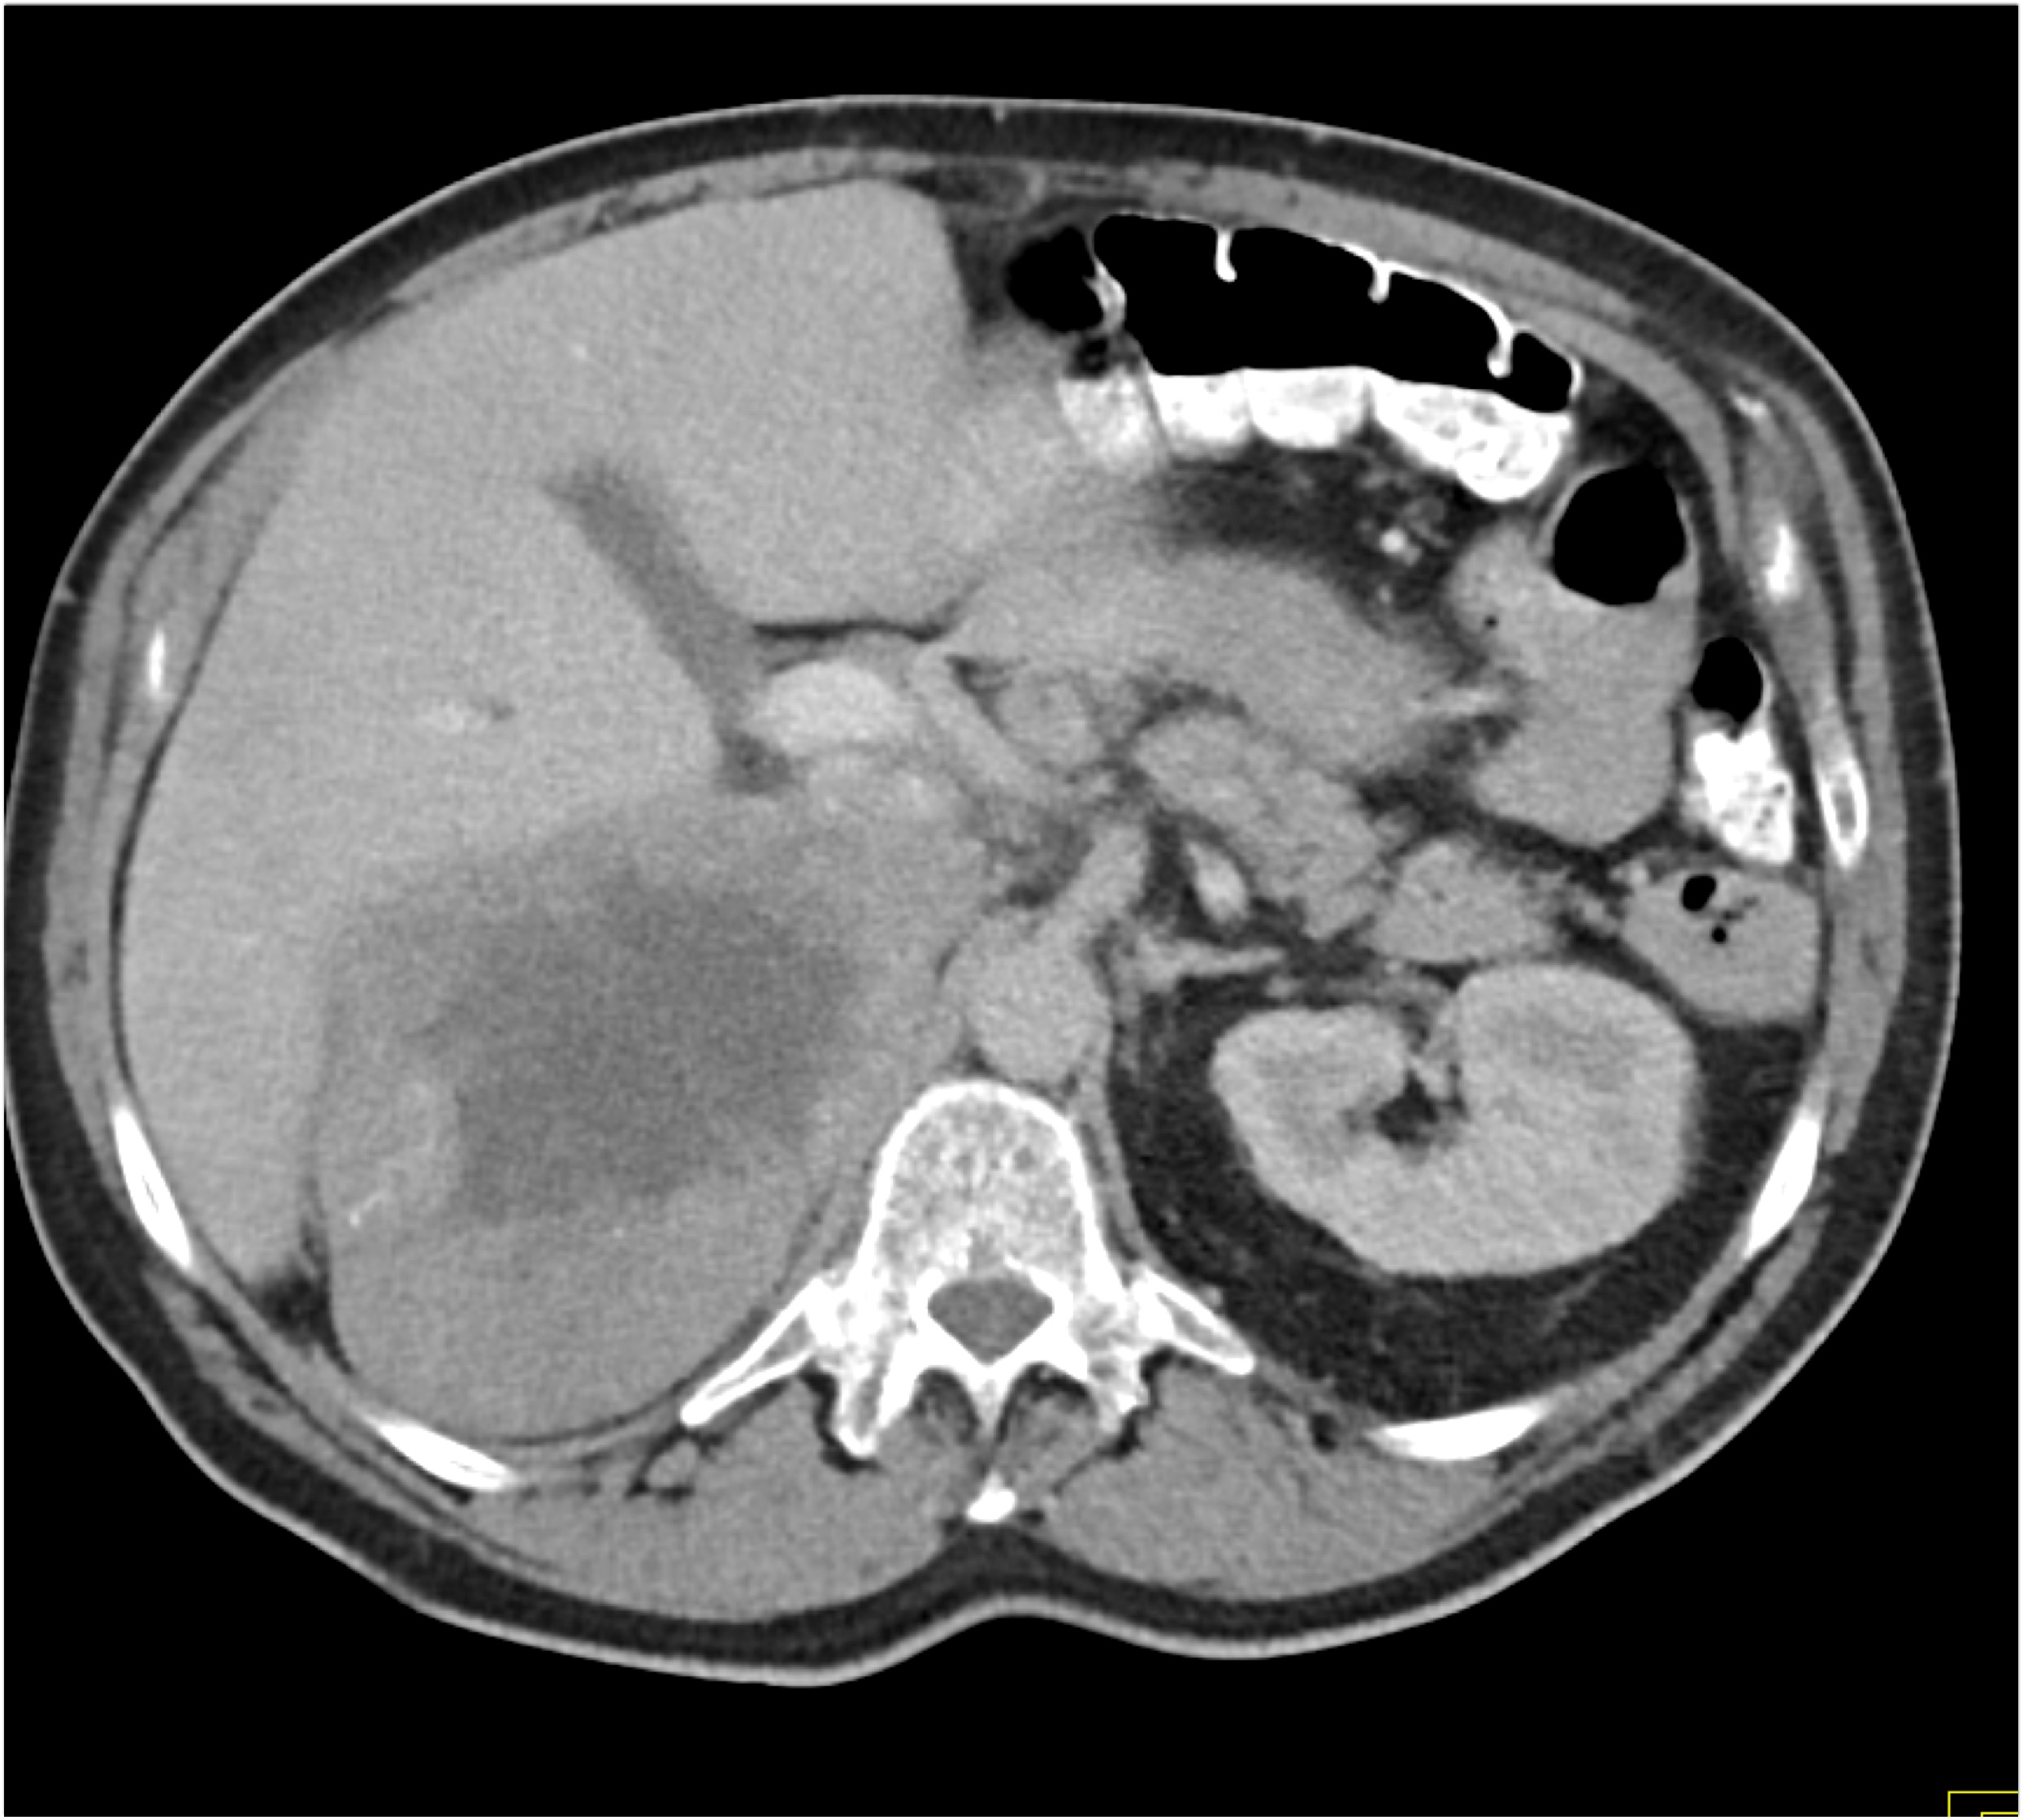

2) The least likely diagnosis in this case is?

hepatoma

cholangiocarcinoma

metastatic disease to the liver

hemangioma